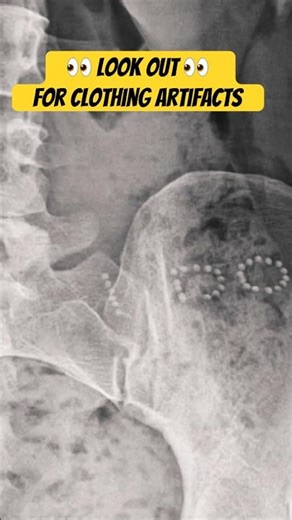

Clothing Artifacts on X-Ray

已浏览 1508 次

2024年3月30日

YouTube

X-Ray Review: Learn Radiology Fast!